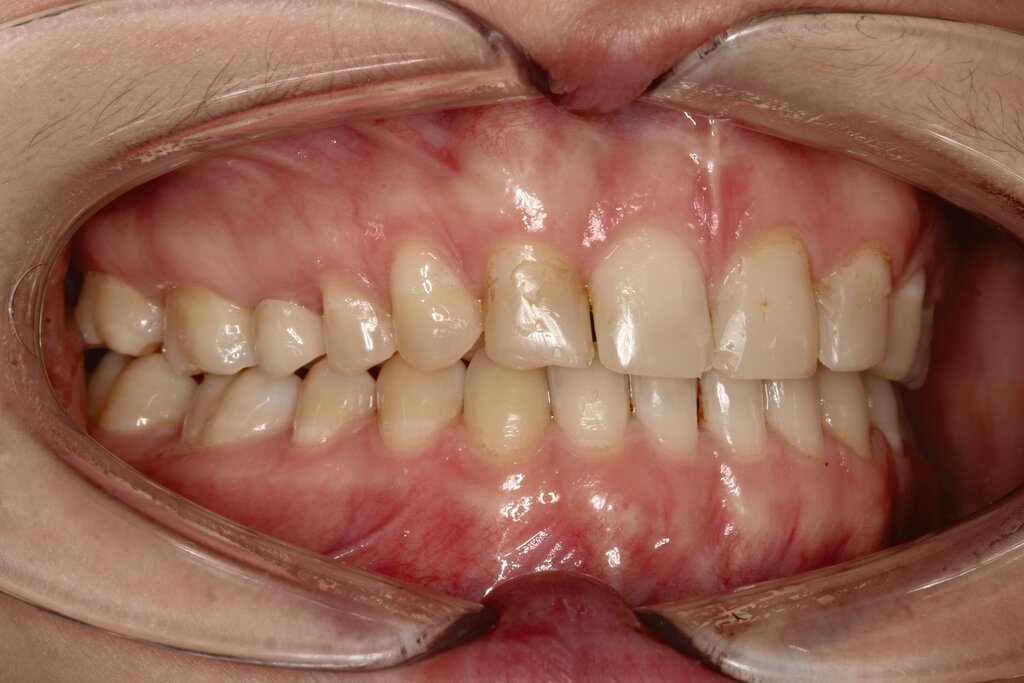

Im vorliegenden Fall stand der Zahn 23 bereits im Mesialstand bei hoher Lachlinie und tendenziell konkavem Lippenprofil. Bezüglich Morphologie und Farbe waren die Zähne 13 und 23 nicht ausgeprägt eckzahntypisch. Es bestand kein Platzmangel im Gegenkiefer. Die Patientin war bei der Erstdiagnose 12,5 Jahre alt und im Wechselgebiss der zweiten Phase mit atypischer Durchbruchreihenfolge. Es bestand eine geringfügige Klasse II. Der Overjet war vergrößert bei vertikaler Wachstumstendenz, der Overbite war um circa einen Millimeter vergrößert aufgrund der geringfügigen Steilstellung der Oberkiefer-Front. Es bestand der Verdacht auf Nichtanlage der Weisheitszähne, 15 und 25 waren verlagert.

Daher wurde ein Lückenmanagement mit Lückenschluss in der Oberkiefer-Front und Lückenöffnung mesial 16 und 26 außerhalb der ästhetischen Zone angestrebt. Eine implantatprothetische Versorgung kam aufgrund des jungen Alters der Patientin nicht infrage. Die Autotransplantation eines Prämolaren war ebenfalls ausgeschlossen, da kein Engstand und keine Indikation zur Ausgleichsextraktion bestanden.